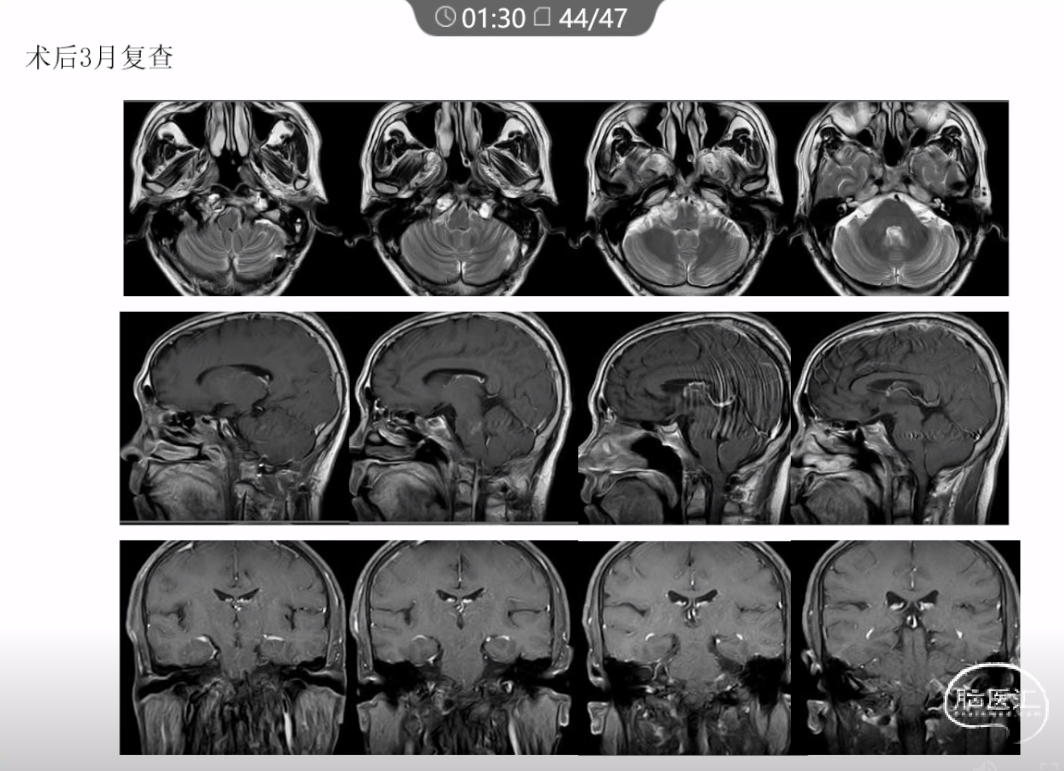

本文主要内容为:脊索瘤临床特点、治疗选择,以及多个手术病例。